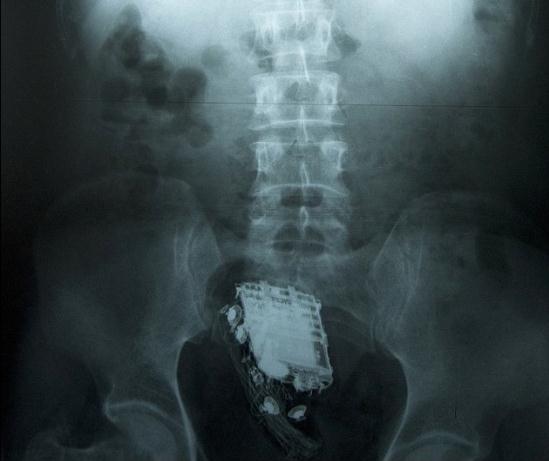

这名58岁的男子因偷盗罪被判处10年监禁,目前正在斯里兰卡首都科伦坡的韦利卡达监狱服刑。为了能把手机顺利取出,狱警后来把他送进了医院。X射线扫描显示,手机被深深地塞进了直肠里。